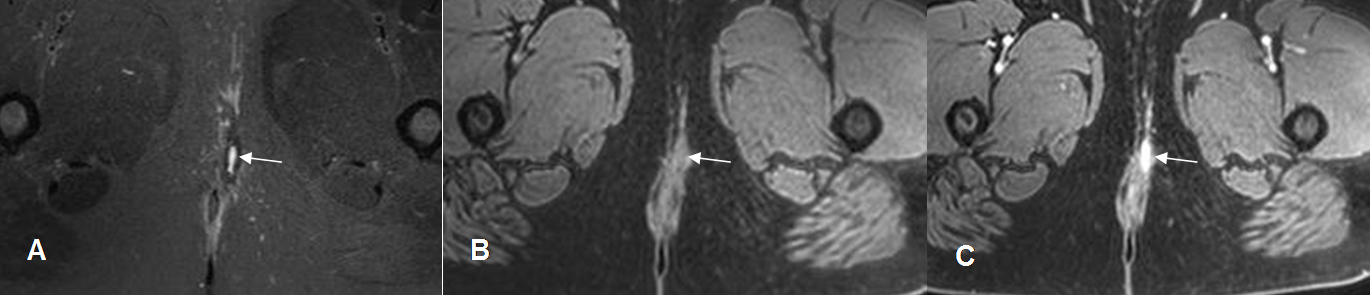

Fig 45 B. Osteomielitis crónica.

A: Rx AP. PostQx de fracturas expuestas en la pierna y clínicamente cambios inflamatorios en la extremidad. Hay fractura parcialmente consolidada de la tibia, fijada con clavo endomedular. Prominencia de los tejidos blandos e imágenes radiolúcidas que hacen sospechar la presencia de aire.

B y C: RM axial en T2. Cambios inflamatorios en los tejidos blandos, con múltiples colecciones que rodean el foco de fractura. Dentro de la colecciones en C, hay imágenes alargadas e hipointensas, que corresponden a burbujas de aire.

Fig 45 C. Osteomielitis crónica.

A: RM sagital en T2 y B: RM sagital en STIR. Igual paciente anterior. Se encuentra trayecto fistuloso que se origina en el foco de fractura y comunica con una colección, por osteomielitis crónica.